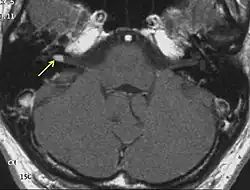

The so-called acoustic neuroma of NF2 is in fact a schwannoma of the nervus vestibularis, or vestibular schwannoma. The misnomer of acoustic neuroma is still often used. The vestibular schwannomas grow slowly at the inner entrance of the internal auditory meatus (meatus acousticus internus). They derive from the nerve sheaths of the upper part of the nervus vestibularis in the region between the central and peripheral myelin (Obersteiner-Redlich-Zone) within the area of the porus acousticus, 1 cm from the brainstem.

NF2 is a genetically transmitted condition. Diagnosis is most common in early adulthood (20–30 years); however, it can be diagnosed earlier. NF2 can be diagnosed due to the presence of a bilateral vestibular schwannoma, or an acoustic neuroma, which causes a hearing loss that may begin unilaterally.[14] If a patient does not meet this criterion of diagnosis, they must have a family history of NF2, and present with a unilateral vestibular schwannoma and other associated tumors (cranial meningioma, cranial nerve schwannoma, spinal meningioma, spinal ependymomas, peripheral nerve tumor, spinal schwannoma, subcutaneous tumor, skin plaque). This being said, more than half of all patients diagnosed with NF2 do not have a family history of the condition.[14] Although it has yet to be included into clinical classification, peripheral neuropathy, or damage to the peripheral nerves, which often causes weakness, numbness and pain in the hands and feet, may also lead to a diagnosis of NF2. In children, NF2 can present with similar symptoms, but generally causes "visual disturbances (cataracts, hamartomas), skin tumors, mononeuropathhy (facial paresis, drop foot), symptomatic spinal cord tumors, or non-vestibular intracranial tumors".[14]

Bilateral vestibular schwannomas are diagnostic of NF2.[15]